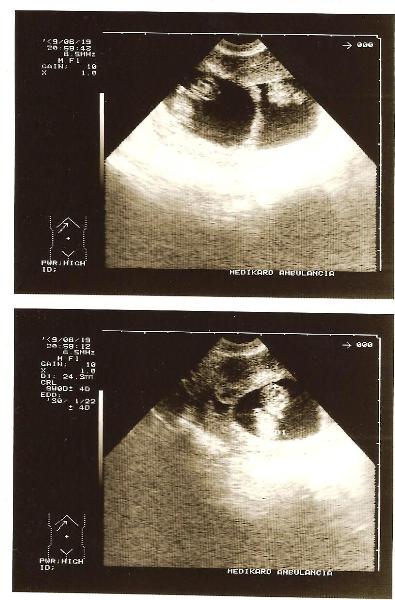

Reunion, gyönyörűek az ikreid, olyan jó ilyen UH-t is látni